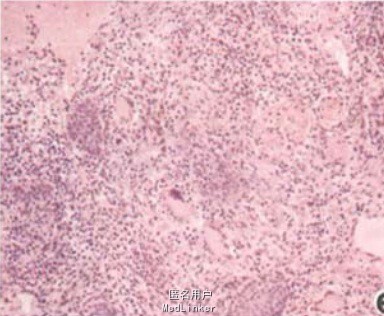

皮肤科检查:头颅向左前方偏斜30度左右,活动受限.不能正位。胸部见一约12 cm×12cm不规则环形红丘疹、斑块,边界清,边缘隆起,颜色鲜红,中央网状瘢痕。右面部见一约8cm×4cm肿块,中等硬度,边缘不清,与周围组织黏连,有压痛。肿块表面可见红斑及多出坏死灶,挤压有黄色粘稠分泌物。左额部、左锁骨下及左足背各有一鸽蛋大肿物,部分呈囊性,活动度佳,边缘较清晰,与周围组织无明显黏连;两侧颈部群集花生米大小淋巴结;均有压痛。实验室检查:分泌物细菌培养出金黄色葡萄球菌。组织病理检查:面部及胸部皮损病检见真皮内见多个上皮样细胞构成的肉芽肿,中央有少许朗格汉斯细胞,结节内及周边有致密的淋巴细胞浸润。锁骨下包块病理检查见多个由上皮样细胞构成的结节,其中央均有大片干酪样坏死灶及不完全坏死灶。颈部肿大淋巴结病检见淋巴结内散在多个大小不等的上皮样细胞结节,抗酸染色阳性;分枝杆菌组织培养阴性;PAS染色阴性; PPD强阳性。